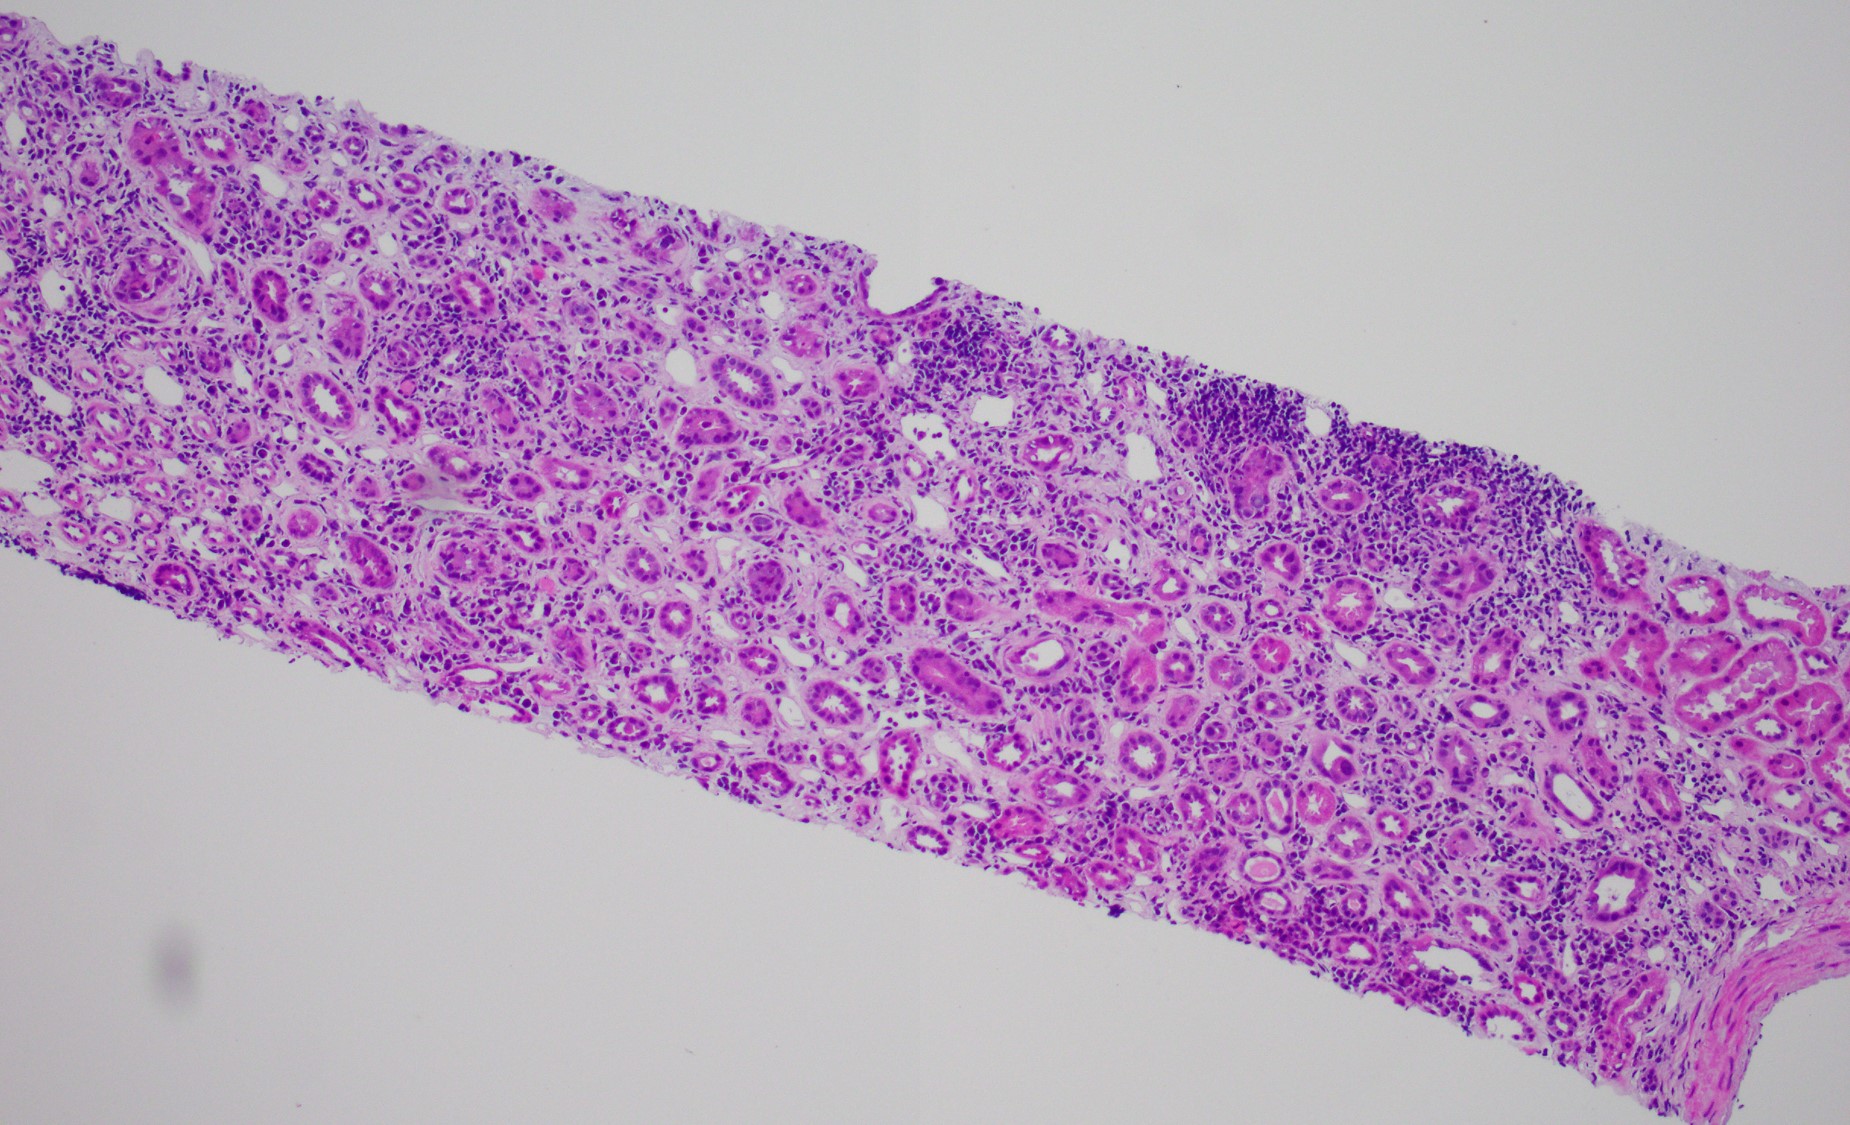

It is not always easy of straightforward to distinguish BK nephropathy from acute rejection, and very difficult to diagnose a coexisting lesion including both of them. T cell-mediated rejection shares similar histopathologic features with BK nephropathy, such as focal and brisk interstitial inflammation and tubulitis (shown in Fig. 1). However, typical viral cytopathic changes are more common in BK nephropathy, such as nuclear enlargement and intranuclear infusion (Fig. 2, yellow arrow) and features resenbling so called "decoy cells" in urine cytology (Fig. 2, red arrow). SV-40 large T antigen staining with IHC confirms a diagnosis of polyomavirus infection (shown in Fig. 3), but can't differentiate BK from JC virus. Interestingly, some patients with BK nephropathy shows C4d deposits in the tubular basement membrane (Fig. 4), but not the typical pattern of peritubular linear C4d stain for antibody-mediate rejection.